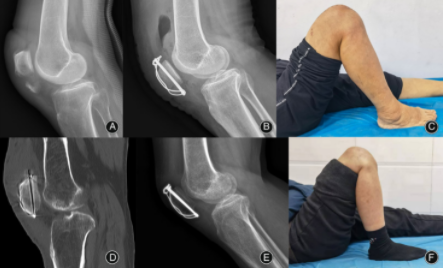

图3. 病例(例4,55岁,男性,右侧)。术前正位(A)和侧位(B) x线片显示髌骨下极移位骨折。术后正位(C)和侧位(D) x线片。2年随访时的x线片(E-F)和功能(G-I)。

扎骨针怎么装髌骨下极粉碎骨折怎么办?7种固定技术详解与术式选择_https://www.jmylbn.com_新闻资讯_第10张

图4. 病例示例(45岁,女性,右侧)。术前正位(A)和侧位(B) x线片显示髌骨下极移位骨折。术后正位(C)和侧位(D) x线片。术后19个月复查x线片(E、F)和功能(G-I)。